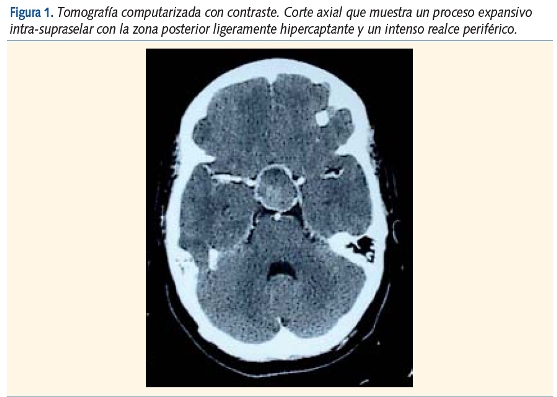

La tomografía computarizada (TC) descubrió un proceso expansivo intraselar (emergía desde el interior de la silla turca) con crecimiento supraselar, bien delimitado, de unos 3 cm de diámetro máximo, isodenso respecto al parénquima, de aspecto quístico con polo sólido y anillo periférico hipercaptantes tras la inyección de contraste (figura 1).